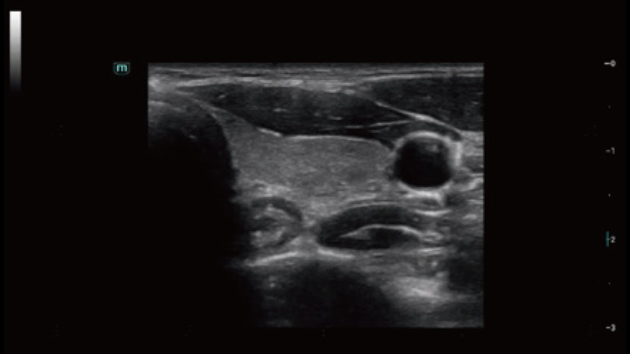

Comprehensive Imaging Solutions Powered by ZST+

The ZST+ platform is an extraordinary innovation, representing an ultrasound evolution. Transforming ultrasound metrics from conventional beam-forming to channel data based processing. It overcomes the traditional trade-off limitation among spatial resolution, temporal resolution and tissue uniformity, delivering exceptional image quality for infinite imaging solutions with non-stop improvements.